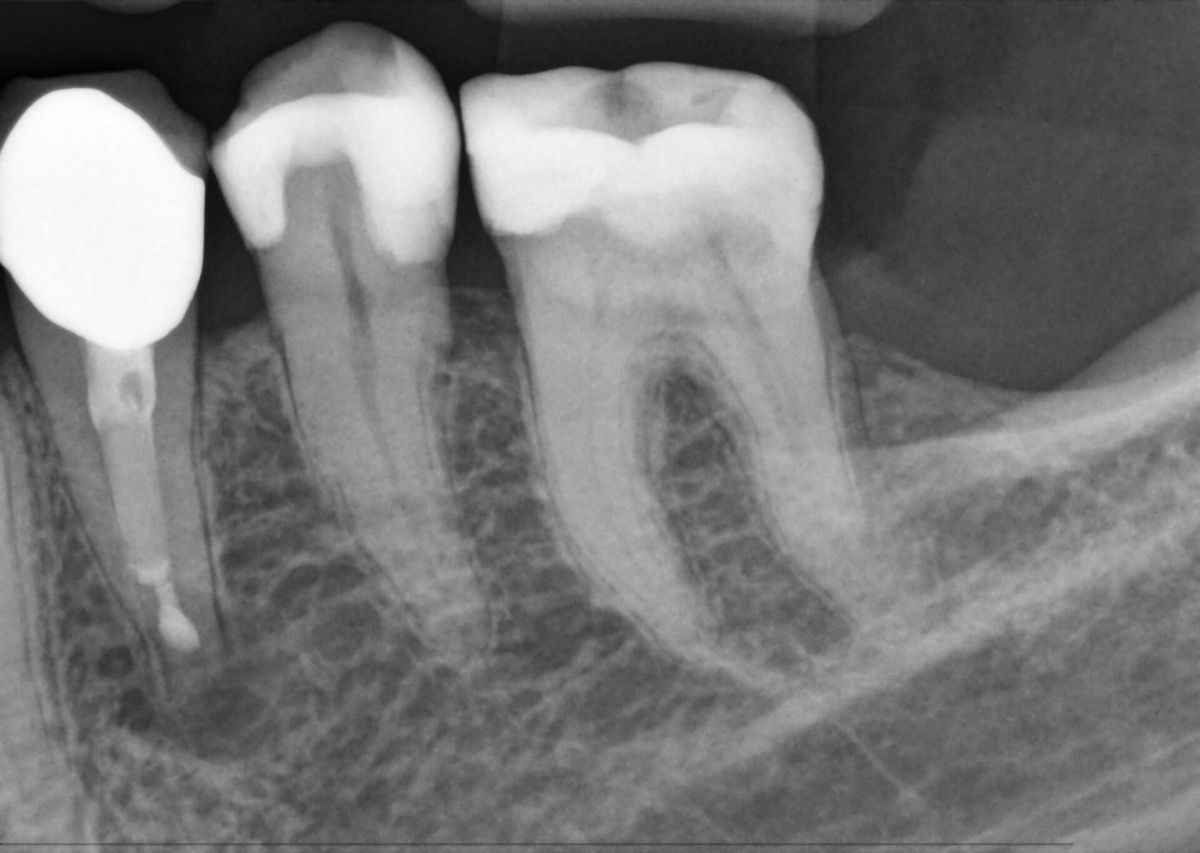

MARS: software de reducción de artefactos metálicos

Los artefactos metálicos suponen un reto en lo que respecta a la radiografía 3D. Los objetos radiopacos crean efectos de sombra y rayas durante la reconstrucción tridimensional y, por lo tanto, interfieren en los resultados. El MARS reduce automáticamente los artefactos metálicos y facilita el diagnóstico.

Sensores intraorales Xios AE: Rango dinámico mejorado

La sensibilidad de sensor aumentada y un espectro de exposición optimizado con dosis baja mejorada permiten una visibilidad óptima y diagnósticos con una exposición muy reducida. Las imágenes con baja exposición se compensan con éxito, proporcionando una calidad de imagen consistente y flexibilidad en lo que respecta a la dosis.